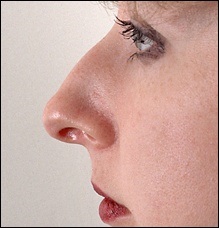

A fénykép a bal oldalon mutatja egy ember tipikus megnövekedett nazális gerinc. Ez jelentősen növeli az orrát előre. A fénykép után a művelet ugyanaz az ember nagyon jól néz ki.

Ebben a beteg, ott van a hatás a „kötés” a felső ajak. Photo fenti elégedett üzemeltetés előtt. Fekete jelzi a helyzetét az első kiálló orr-gerinc. A kék vonalat húzott a jobb megítélése a profilt. Ha a hatása „árukapcsolás” a felső ajak vonal irányította a profilját Vered és legfeljebb az alap az orr.

Az operáció utáni képek labrum irányban függőlegesen felfelé.